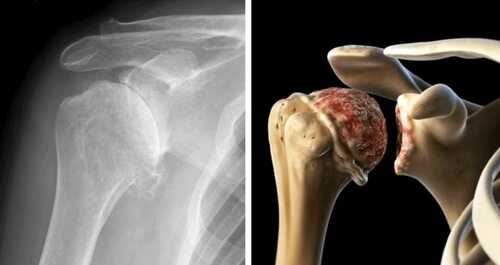

Фото артроза плечевого сустава

Ниже представлены фотографии, которые помогут вам лучше понять, как выглядит артроз плечевого сустава:

(Фото 2)